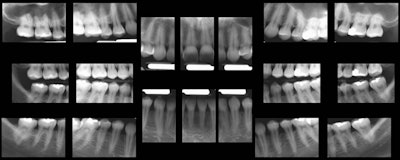

These are 18 separate intraoral images of the same patient, taken with an intraoral camera.